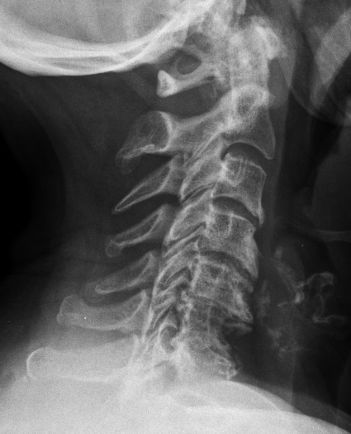

62-jährige Frau mit multiplem Myelom![]() |

![]() | ||